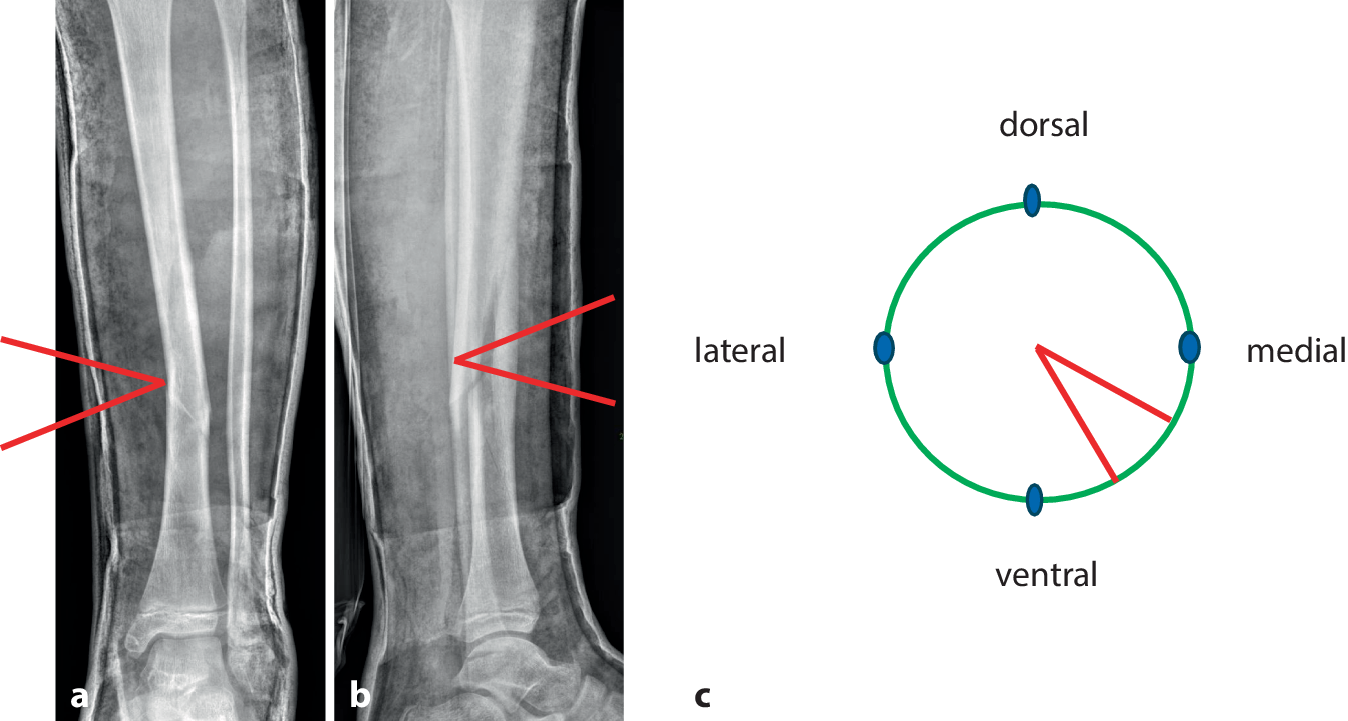

Abb. 6

Zunächst minimales Aufspreizen des Gipses, dies sollte im zentralen Bereich der Markierung erfolgen, um ein Maximum an Hebelwirkung in der Konkavität der Fraktur zu erzielen (ab). Passageres Einlegen eines Platzhalters und etwas Zuwarten (c). Wichtig ist die Kommunikation mit dem Patienten, bis auf geringe Beschwerden im Frakturbereich am Ende des Keilungsvorganges muss die Behandlung im Wesentlichen schmerzfrei sein

Abb. 7

Schrittweise dosiertes weiteres Aufspreizen, wobei zum Offenhalten des vergrößerten Spaltes bis zum Einlegen des neuen Keils ein zweiter Spreizer zum Einsatz kommt. Ein „leichtes Ziehen“ in Frakturhöhe signalisiert meist die richtige Größe des Keils. a Dosiertes weiteres Aufspreizen, b größerer Keil als passagerer Platzhalter, c Positionierung des definitiven Keils